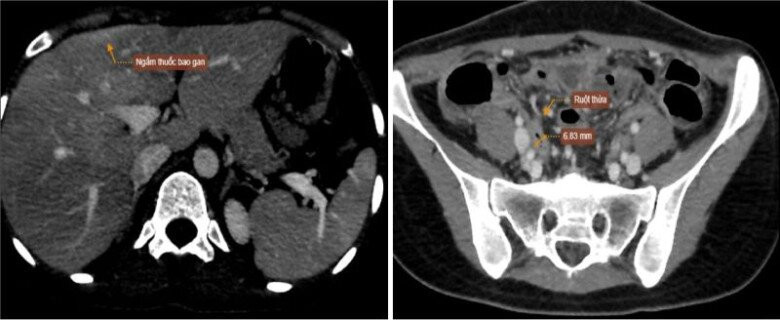

Chị Đ.T.T (31 tuổi, ở Hà Nội) thời gian gần đây xuất hiện tình trạng đau lan dọc mạn sườn, hố chậu phải, cơn đau bụng tăng khi hít thở mạnh, thay đổi tư thế đột ngột, kèm theo ít khí hư âm đạo bất thường nên đến viện thăm khám. Sau khi thăm khám, chị T được chỉ định siêu âm, xét nghiệm và nghi ngờ có tình trạng nhiễm trùng. Chụp cắt lớp vi tính kết quả cho thấy, có tình trạng bao gan dày, ngấm thuốc mạnh, dày nhẹ các quai ruột, thâm nhiễm mỡ vùng tiểu khung, ruột thừa tăng kích thước nhẹ.

Hình ảnh chụp cắt lớp vi tính ổ bụng của bệnh nhân. Ảnh: BSCC.

Từ những kết quả trên, bác sĩ chẩn đoán chị T mắc hội chứng Fitz-Hugh-Curtis, do viêm phụ khoa từ vùng tiểu khung gây ra và được chỉ định điều trị nội trú tại bệnh viện. Sau 5 ngày điều trị nội trú tích cực, chị T. hết sốt, hết đau bụng, không ra dịch âm đạo bất thường, sức khỏe ổn định và được ra viện uống thuốc theo đơn.